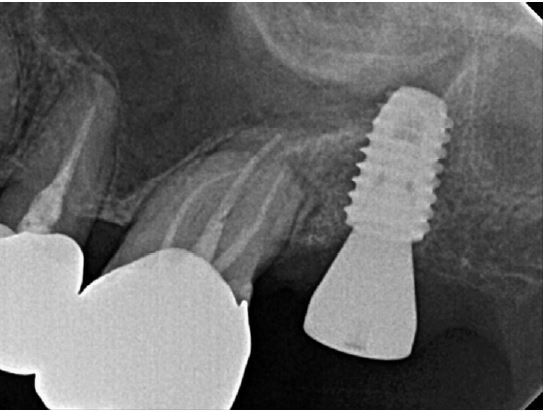

Clinical examination revealed grade 3 mobility with the gingival recession of the distal root of the left mandibular first molar (#36). Radiographic examination confirmed apically involved alveolar bone loss around the mandibular left first molar, however, at a sufficient distance from the mandibular canal (Fig. 1). It was determined that initial stability could be achieved in the apical area, and extraction and iARP were planned. The patient was instructed to rinse with 0.12% chlorhexidine digluconate solution (hexamedine; Bukwang, Seoul, Korea) for 2 min for oral disinfection. The mandibular left first molar was extracted using luxators and extraction forceps under local anesthesia with 2% lidocaine containing 1:80,000 epinephrine (Huons Lidocaine; Huons, Seoul, Korea) (Fig. 2A, 2B). After debridement of granulation tissues and irrigation with sterile normal saline solution, immediate implant placement (TS III 5.0 × 8.5 mm; OSSTEM, Seoul, Korea) was performed (Fig. 2C). The implant was placed 1 mm apical to the lingual socket wall, and the buccal side showed the exposure of two threads of the fixture (Fig. 2D). The implant stability quotient (ISQ) value at 1st surgery was 63. A gap between the implant surface and extraction socket wall and exposed buccal implant thread was filled with deproteinized bovine bone mineral (DBBM) (Bio-Oss®; Geistlich Pharma AG, Wolhusen, Switzerland) and covered with a native bilayer collagen membrane (NBCM) (Bio-Gide®; Geistlich Pharma AG) in a double-layer fashion (Fig. 2E). Subsequently, the hidden X suture and horizontal mattress suture (6-0 Ethilon; Ethicon, Cincinnati, OH, USA) were placed over the NBCM without the intention of primary wound closure (Fig 2F, 2G). Fourteen days after surgery, the patient returned for suture removal and postoperative examination. Healing of the depressed soft tissue above the extraction socket was observed, and a delayed healing pattern of the soft tissue with exposure of the cover screw was observed even after 4 weeks (Fig. 2H, 2I).

Fig. 2.

Case 1: Clinical photographs of the immediate implant placement with alveolar ridge preservation. (A) Gingival recession of the distal root of the left mandibular first molar, (B) Buccal gingival depression observed after tooth extraction, (C) Immediate implant placement in the left mandibular first molar, (D) Two threads of the fixture are exposed on the buccal side, (E) Deproteinized bovine bone mineral was placed in the extraction socket and covered with a native bilayer collagen membrane, (F) Hidden X and horizontal mattress sutures are placed, (G) Panoramic radiograph obtained after implant placement, (H) Depressed gingival healing was observed at stitch out (2 weeks), (I) Cover screw exposure with depressed gingival healing was observed during a recall check (4 weeks).